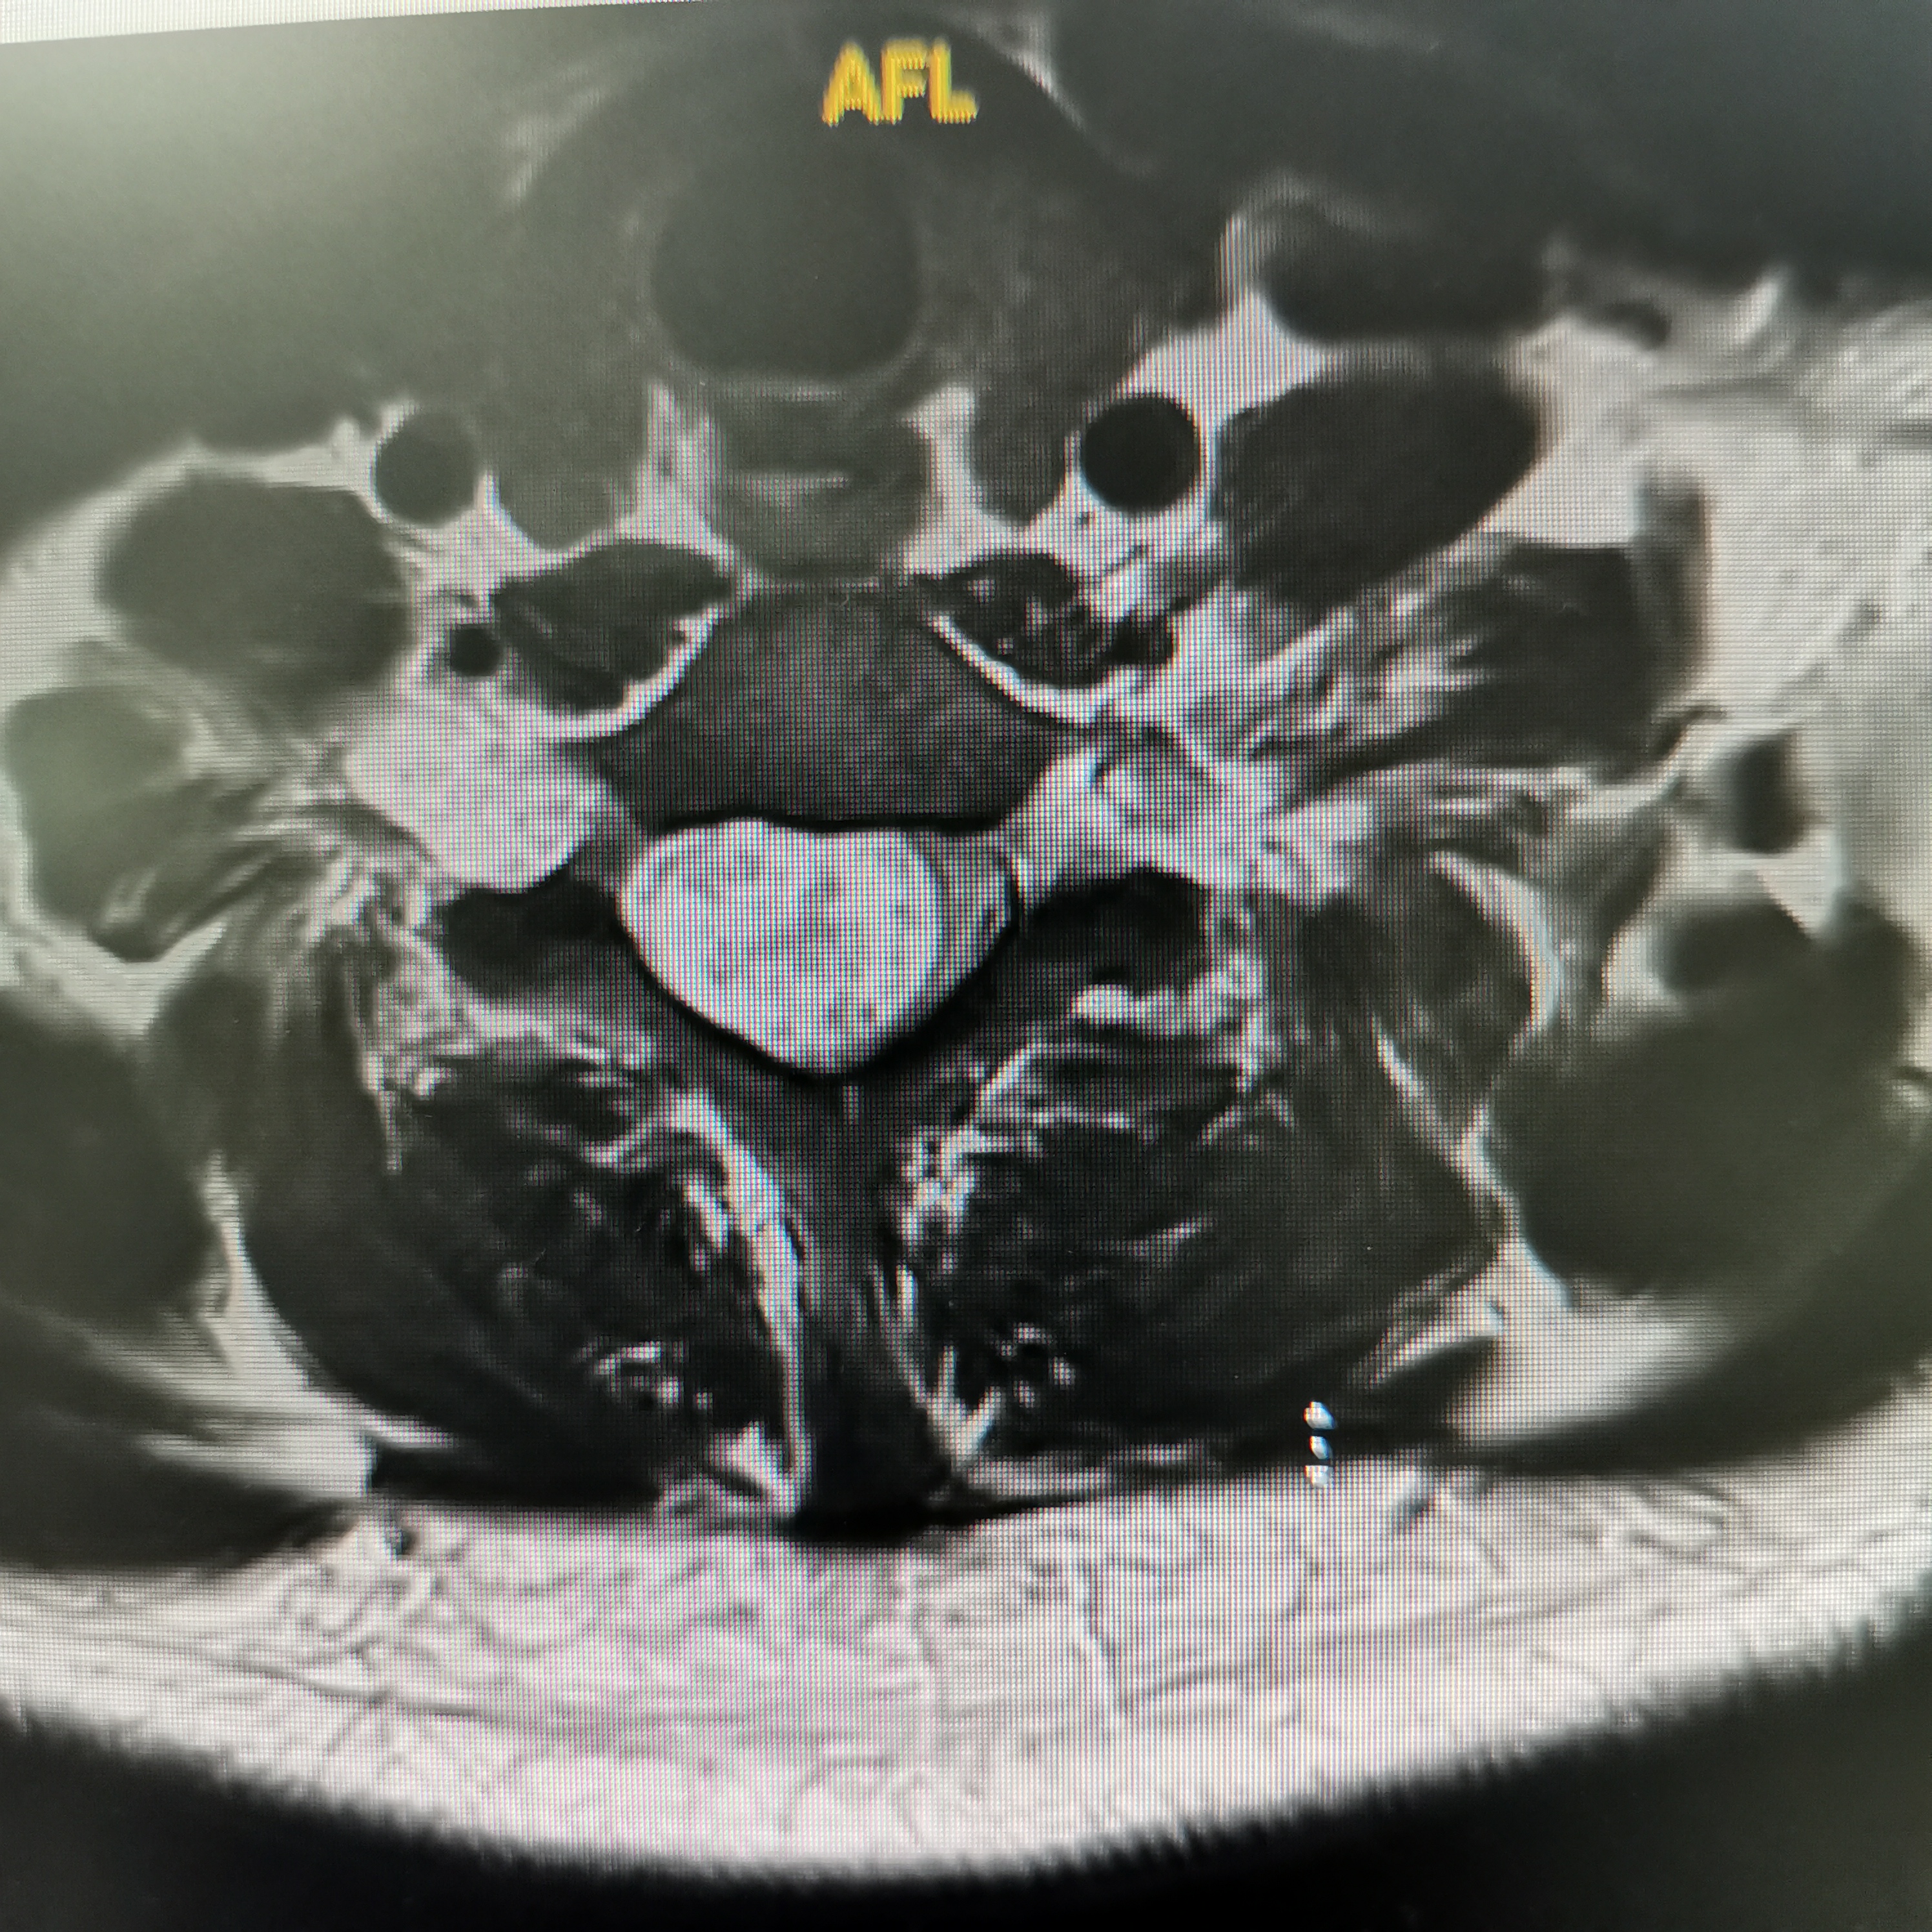

脊髓脊柱-脊髓脊柱肿瘤

神经纤维瘤病的治疗需要综合考虑患者的病情、症状、年龄、身体状况等因素,制定个性化的治疗方案。